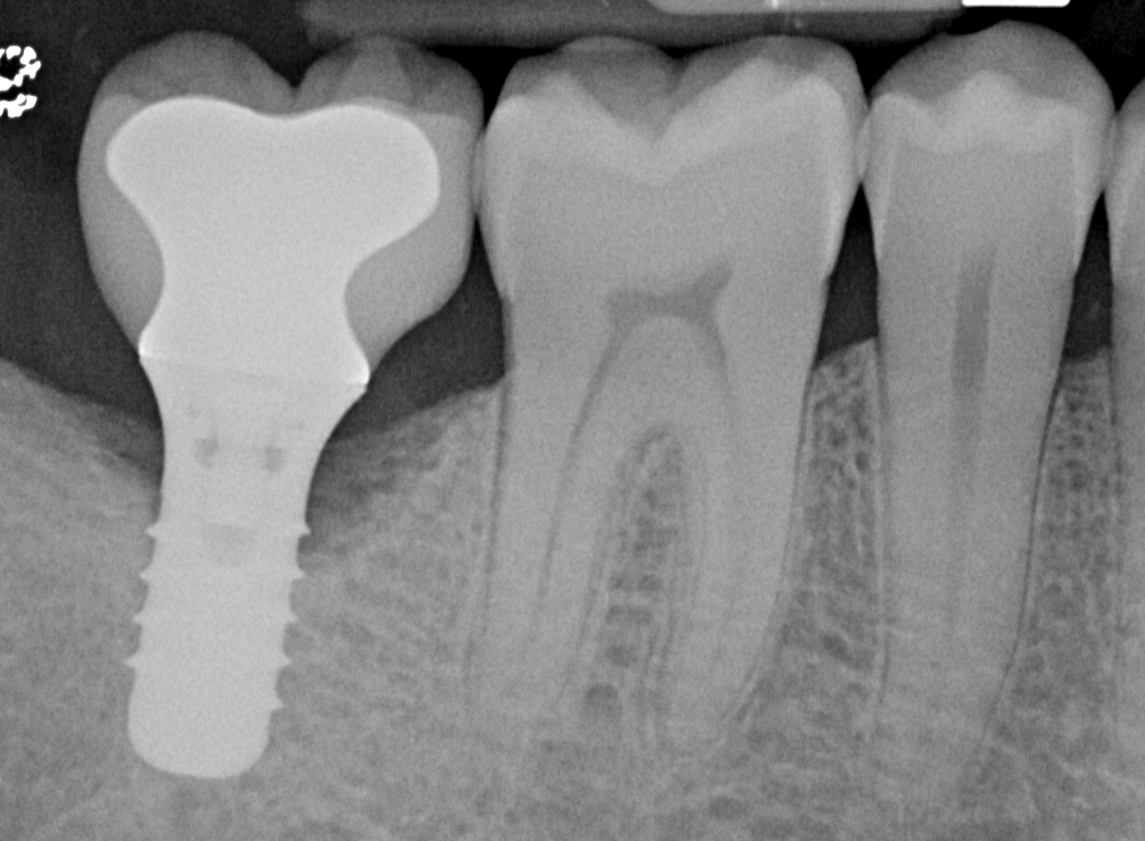

At 1 year following treatment, probing depths are now 3 mm with an absence of bleeding.

Figure 6

Figure 7